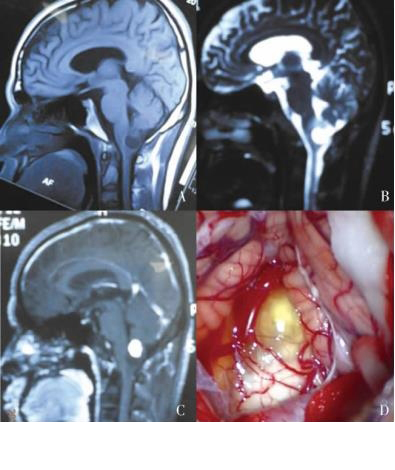

枕骨大孔区肿瘤的MRI 诊断枕骨大孔区肿瘤的MRI检查可清楚的显示肿瘤的位置、大小、质地及与周围脑组织和血管的毗邻关系。根据影像学特点判断肿瘤的性质。神经纤维肿瘤在T1 WI上多表现等或稍低信号,T2 WI上多表现为等或高信号。液化、坏死﹑囊变时表现为长T1、长T2实质性肿瘤强化。囊实性肿瘤囊不强化。T2WI上信号的高低主要取决于肿瘤组织内氢质子数。增强扫描肿瘤常有:均匀强化、不均匀性强化及环行强化,其强化方式反映了肿瘤内有无囊变、液化及坏死等改变。

枕骨大孔区肿瘤手术入路选择需要根据肿瘤的位置及肿瘤与脑干及周围神经血管的位置关系来确定,常用的手术入路包括枕下后正中入路、枕下远外侧入路、经口咽入路。正确的手术入路要能充分暴露肿瘤,避免术中损伤后组脑神经及血管,降低手术后并发症。(1) 枕下后正中入路:此类入路能切除多数的枕骨大孔区的肿瘤,临床上应用比较广泛,适合肿瘤位于枕骨大孔后正中及后外侧者,能直视肿瘤的背侧,侧方和重要的神经血管,利于肿瘤的全部切除。患者取侧卧位或俯卧位,切口上至自枕外隆凸下至上颈部棘突,打开枕骨大孔和咬除部分寰椎后弓后“Y”型剪开硬脊膜。在显微镜下分离枕大池蛛网膜后可清楚的分辨肿瘤组织及肿瘤周围的脑神经及血管。手术切除时要充分保护延颈髓和后组脑神经及全部细小血管、神经。瘤内分块或整体切除肿瘤﹐与延脊髓之间粘连紧密者禁忌强行切除。肿瘤位于髓内者应在神经电生理监测下沿肿瘤离脊髓表面较近处或后正中切开。较大水平切除肿瘤的同时要首先考虑患者的生存质量。

(2) 枕下远外侧入路:此入路直接对着胸锁乳突肌和椎动脉的后方。在枕骨﹑枕课及寰枕关节的内侧。适合肿瘤位于枕骨大孔前方或前外侧者,此入路距离肿瘤近﹐能控制椎动脉近端、远端及其分支和避免对脑干和神经血管的过度牵拉。患者取侧卧或侧俯卧,采用C型或倒L型切口,显露枕下三角时注意保护水平走行的椎动脉及肌支、椎静脉丛。应充分利用枕下三角内的椎静脉丛来保护椎动脉,椎静脉丛的出血可电凝止血或棉片,明胶海绵及止血纱布压迫止血。枕骨课的磨除:若枕骨大孔较大而枕髀较小﹑肿瘤侵蚀枕髃﹑并使脑干向内侧移位时,则不需要磨除枕课。如若需要磨除,部分磨除枕臾可增加寰枕关节腹侧﹑腹外侧及对侧下斜坡的手术视野[12。枕颈的稳定性主要在于枕髀﹑C侧块及附着于上述两者前1/3处翼状韧带和寰椎横韧带的完整性,故枕髃全切除或C侧块和关节面半数以上被磨除者需要行枕颈融合,且瓣状切开硬膜,缓慢释放脑脊液后﹐沿后组脑神经的间隙进行瘤内分块切除,瘤壁塌陷后再沿瘤周蛛网膜间隙进行分离﹐因肿瘤的长期压迫,瘤周和蛛网膜间粘连严重时不可强行分离,避免损伤后组脑神经。术后根据腰穿测压的结果早期行腰大池脑脊液持续体外引流可,减轻血性脑脊液对后组脑神经的刺激及皮下积液的形成,减少术后并发症。